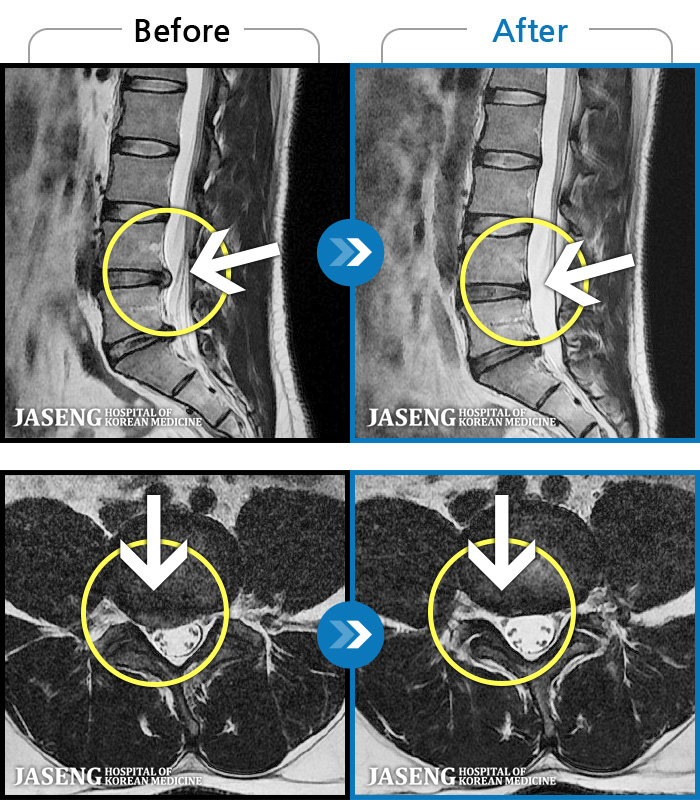

1,257 MRI ũ ʸ Ȯϼ.